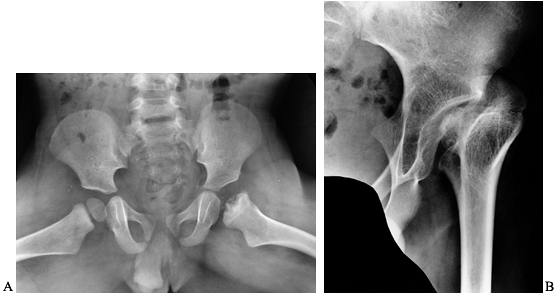

osteonecrosis of the capital femoral epiphysis (Fig. 136.11). More often, hip arthropathy is the result of chronic synovitis, similar to that of the other joints (Fig. 136.12A).

Luck in 1968 (Fig. 136.12B).

|

Figure 136.12. A:

Advanced hemophilic arthropathy of the hip resulting from chronic synovitis with typical joint surface erosions and lateral subluxation. The coxa valga is probably the result of inhibition of abductor function from hemarthroses during growth. B: Cup arthroplasty in the same patient. This was the first major reconstructive procedure performed on a hemophiliac at OHHC. |